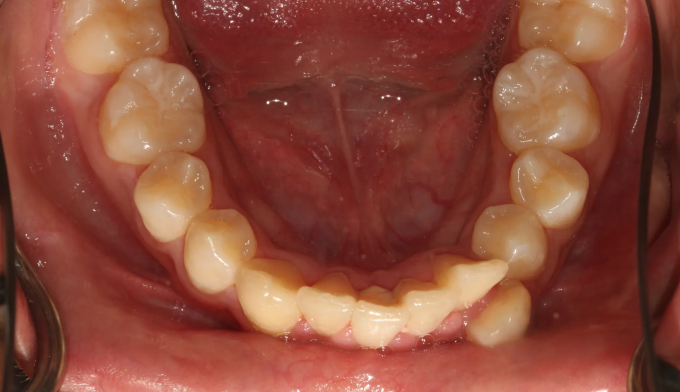

덧니가 심한 학생들, 특히 중,고등학생들을 보면 안타까울때가 종종 있습니다.

조금 더 이른나이에 교정을 시작하였더라면 무리하게 발치하지 않고도 충분히 치아를 가지런하게 할 수 있었을 텐데 라는 생각을 지울수가 없습니다.

이번 케이스도 뒤늦게 송곳니가 덧니로 나오는것을 확인하고 치아교정을 하고자 내원한 중학생입니다.

부족한 공간이 꽤 많고, 입도 돌출되어 보여서 어쩔수 없이 발치교정을 계획하였습니다.

총 치료기간은 23개월입니다.